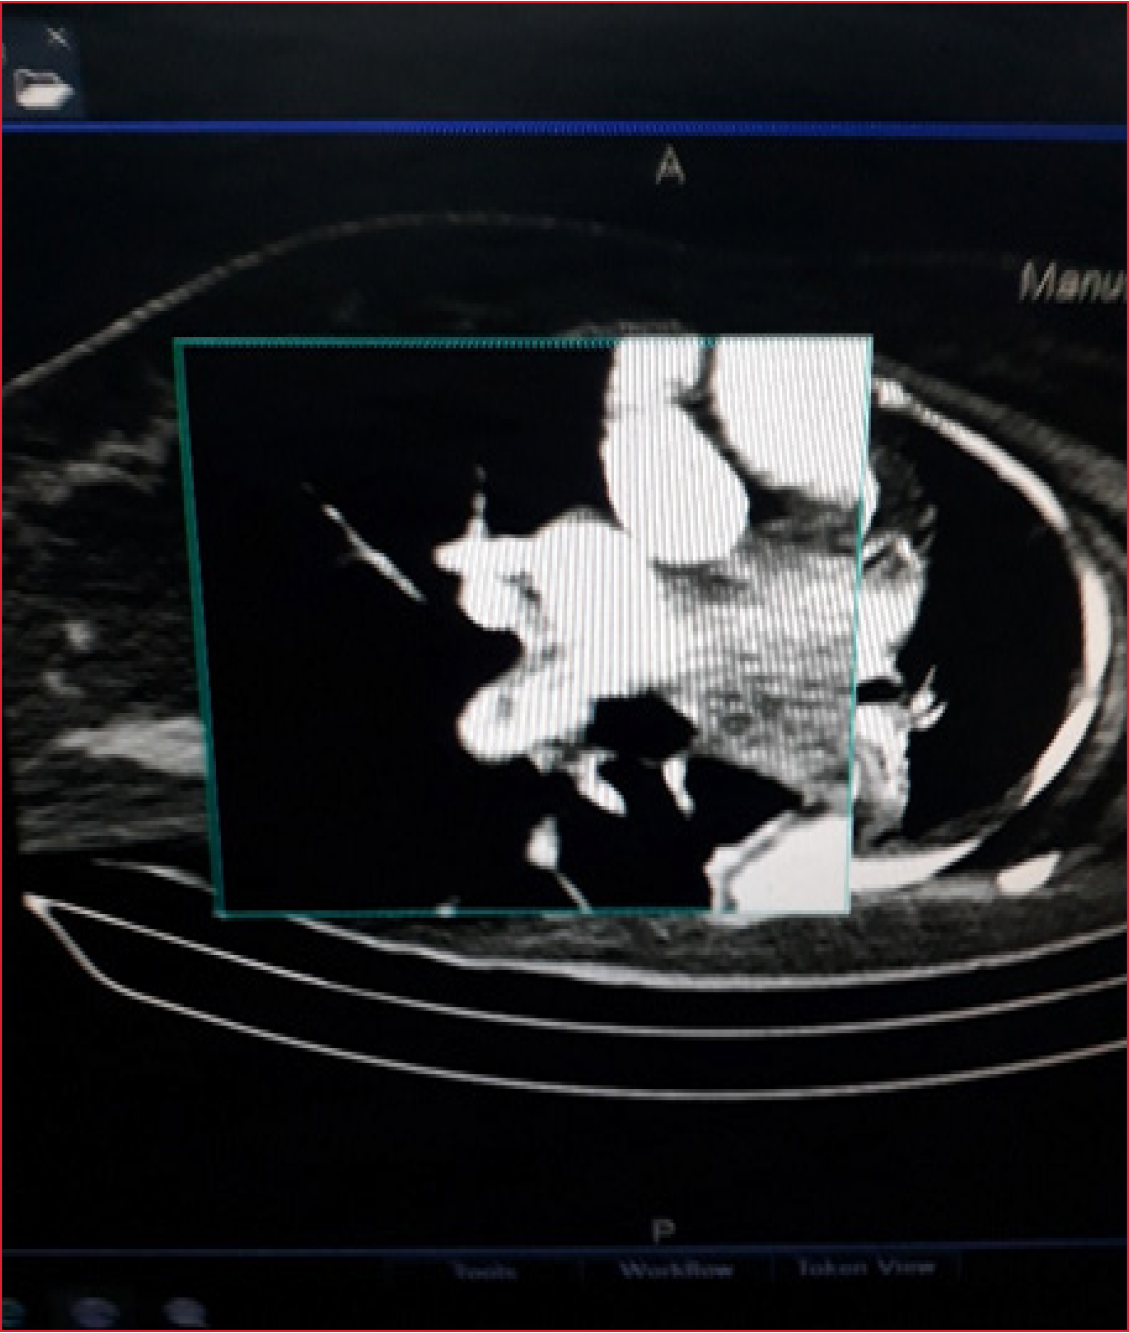

La TC de tórax mostró un tromboembolismo pulmonar parcial de la arteria pulmonar derecha y lesiones inflamatorias en ambas bases pulmonares (Figura 2).

Figura 2. Tomografía computarizada de tórax con contraste intravenoso. Tromboembolismo

parcial de la arteria pulmonar derecha.

En una ecografía Doppler de miembros inferiores, se observó una trombosis venosa profunda en la pierna derecha (poplíteo).

Tras la mejoría inicial, la paciente experimenta una reagudización de la hipoxemia a los 14 días de evolución, por lo que se realiza una angiotomografía que reveló un tromboembolismo pulmonar secundario a la trombosis venosa profunda diagnosticada mediante ecografía Doppler.